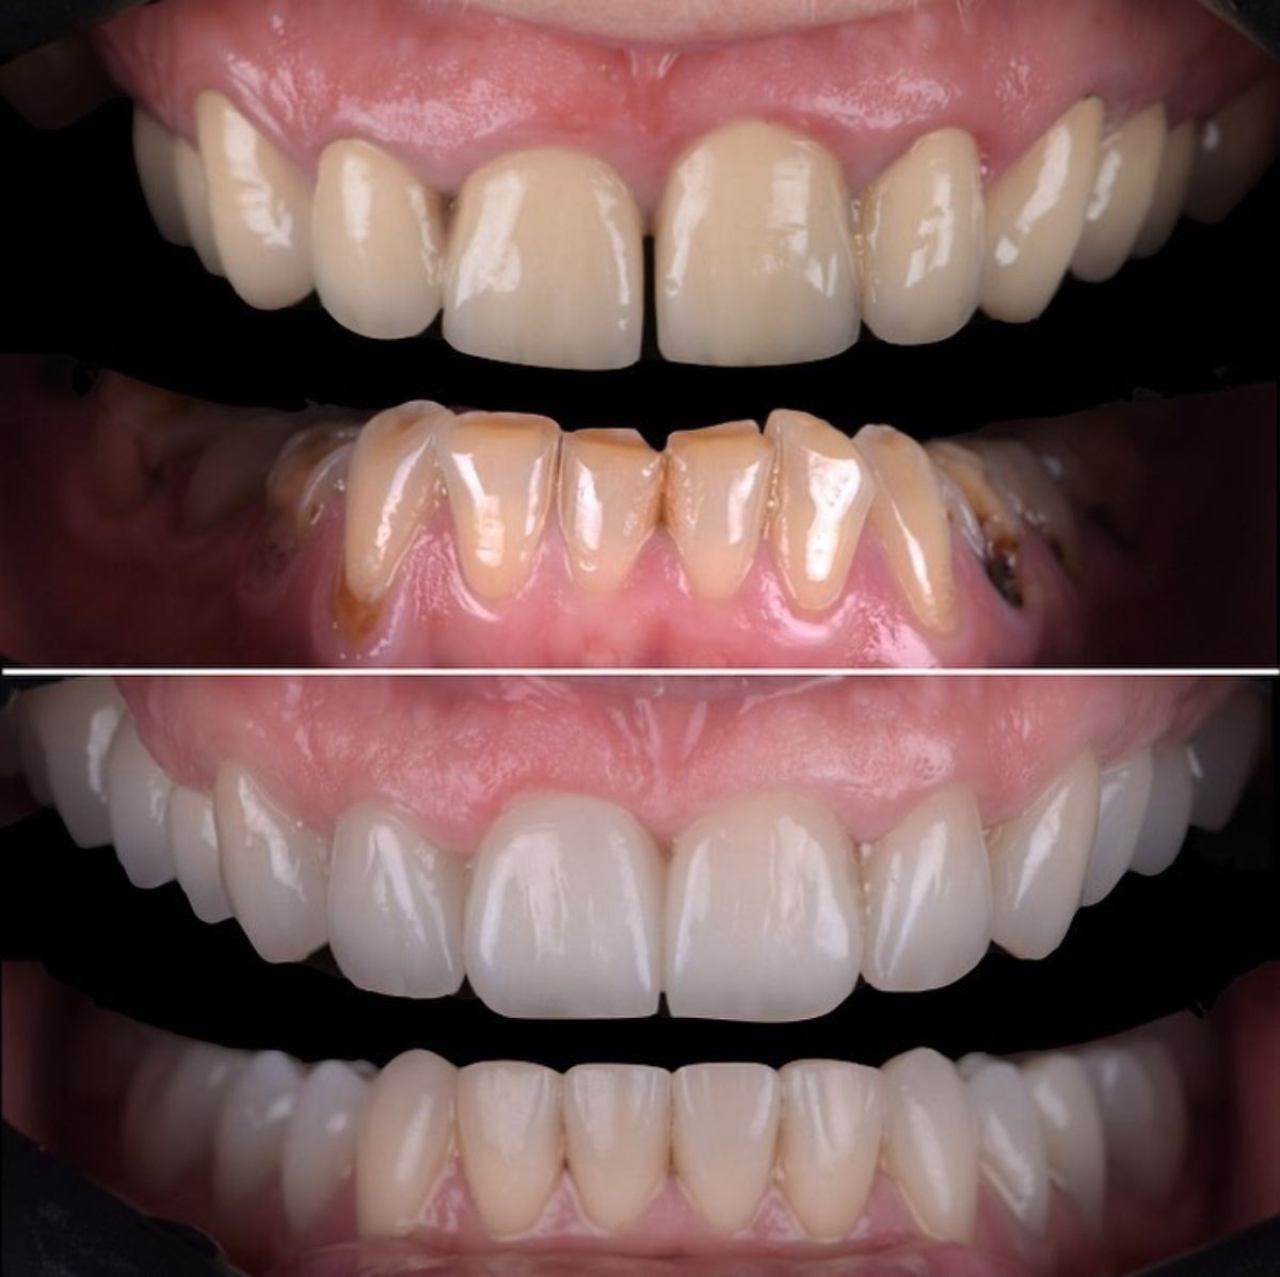

Ljuskice za zube - Veneers

Ljuskice su estetsko rješenje koje vam omogućuje da transformirate svoj osmijeh, trajno se lijepe na prednju površinu zuba i prekrivaju nepravilnosti u obliku, sitne pukotine, diskoloracije ili razmake između zuba.

Koristeći specijalizirane dizajnerske programe i modernu 3D tehnologiju, izrada ljuskica omogućuje precizno reproduciranje karakteristika prirodnih zuba. Osim za estetske razloge, koriste se i kod ispravljanja nepravilnog zagriza i narušene okluzije.

Postavljanje ljuskica je brzo i jednostavno, a rezultati su odmah vidljivi. Vaši zubi će izgledati prirodno lijepo, a vi ćete se osjećati samopouzdano svaki put kada se nasmijete!